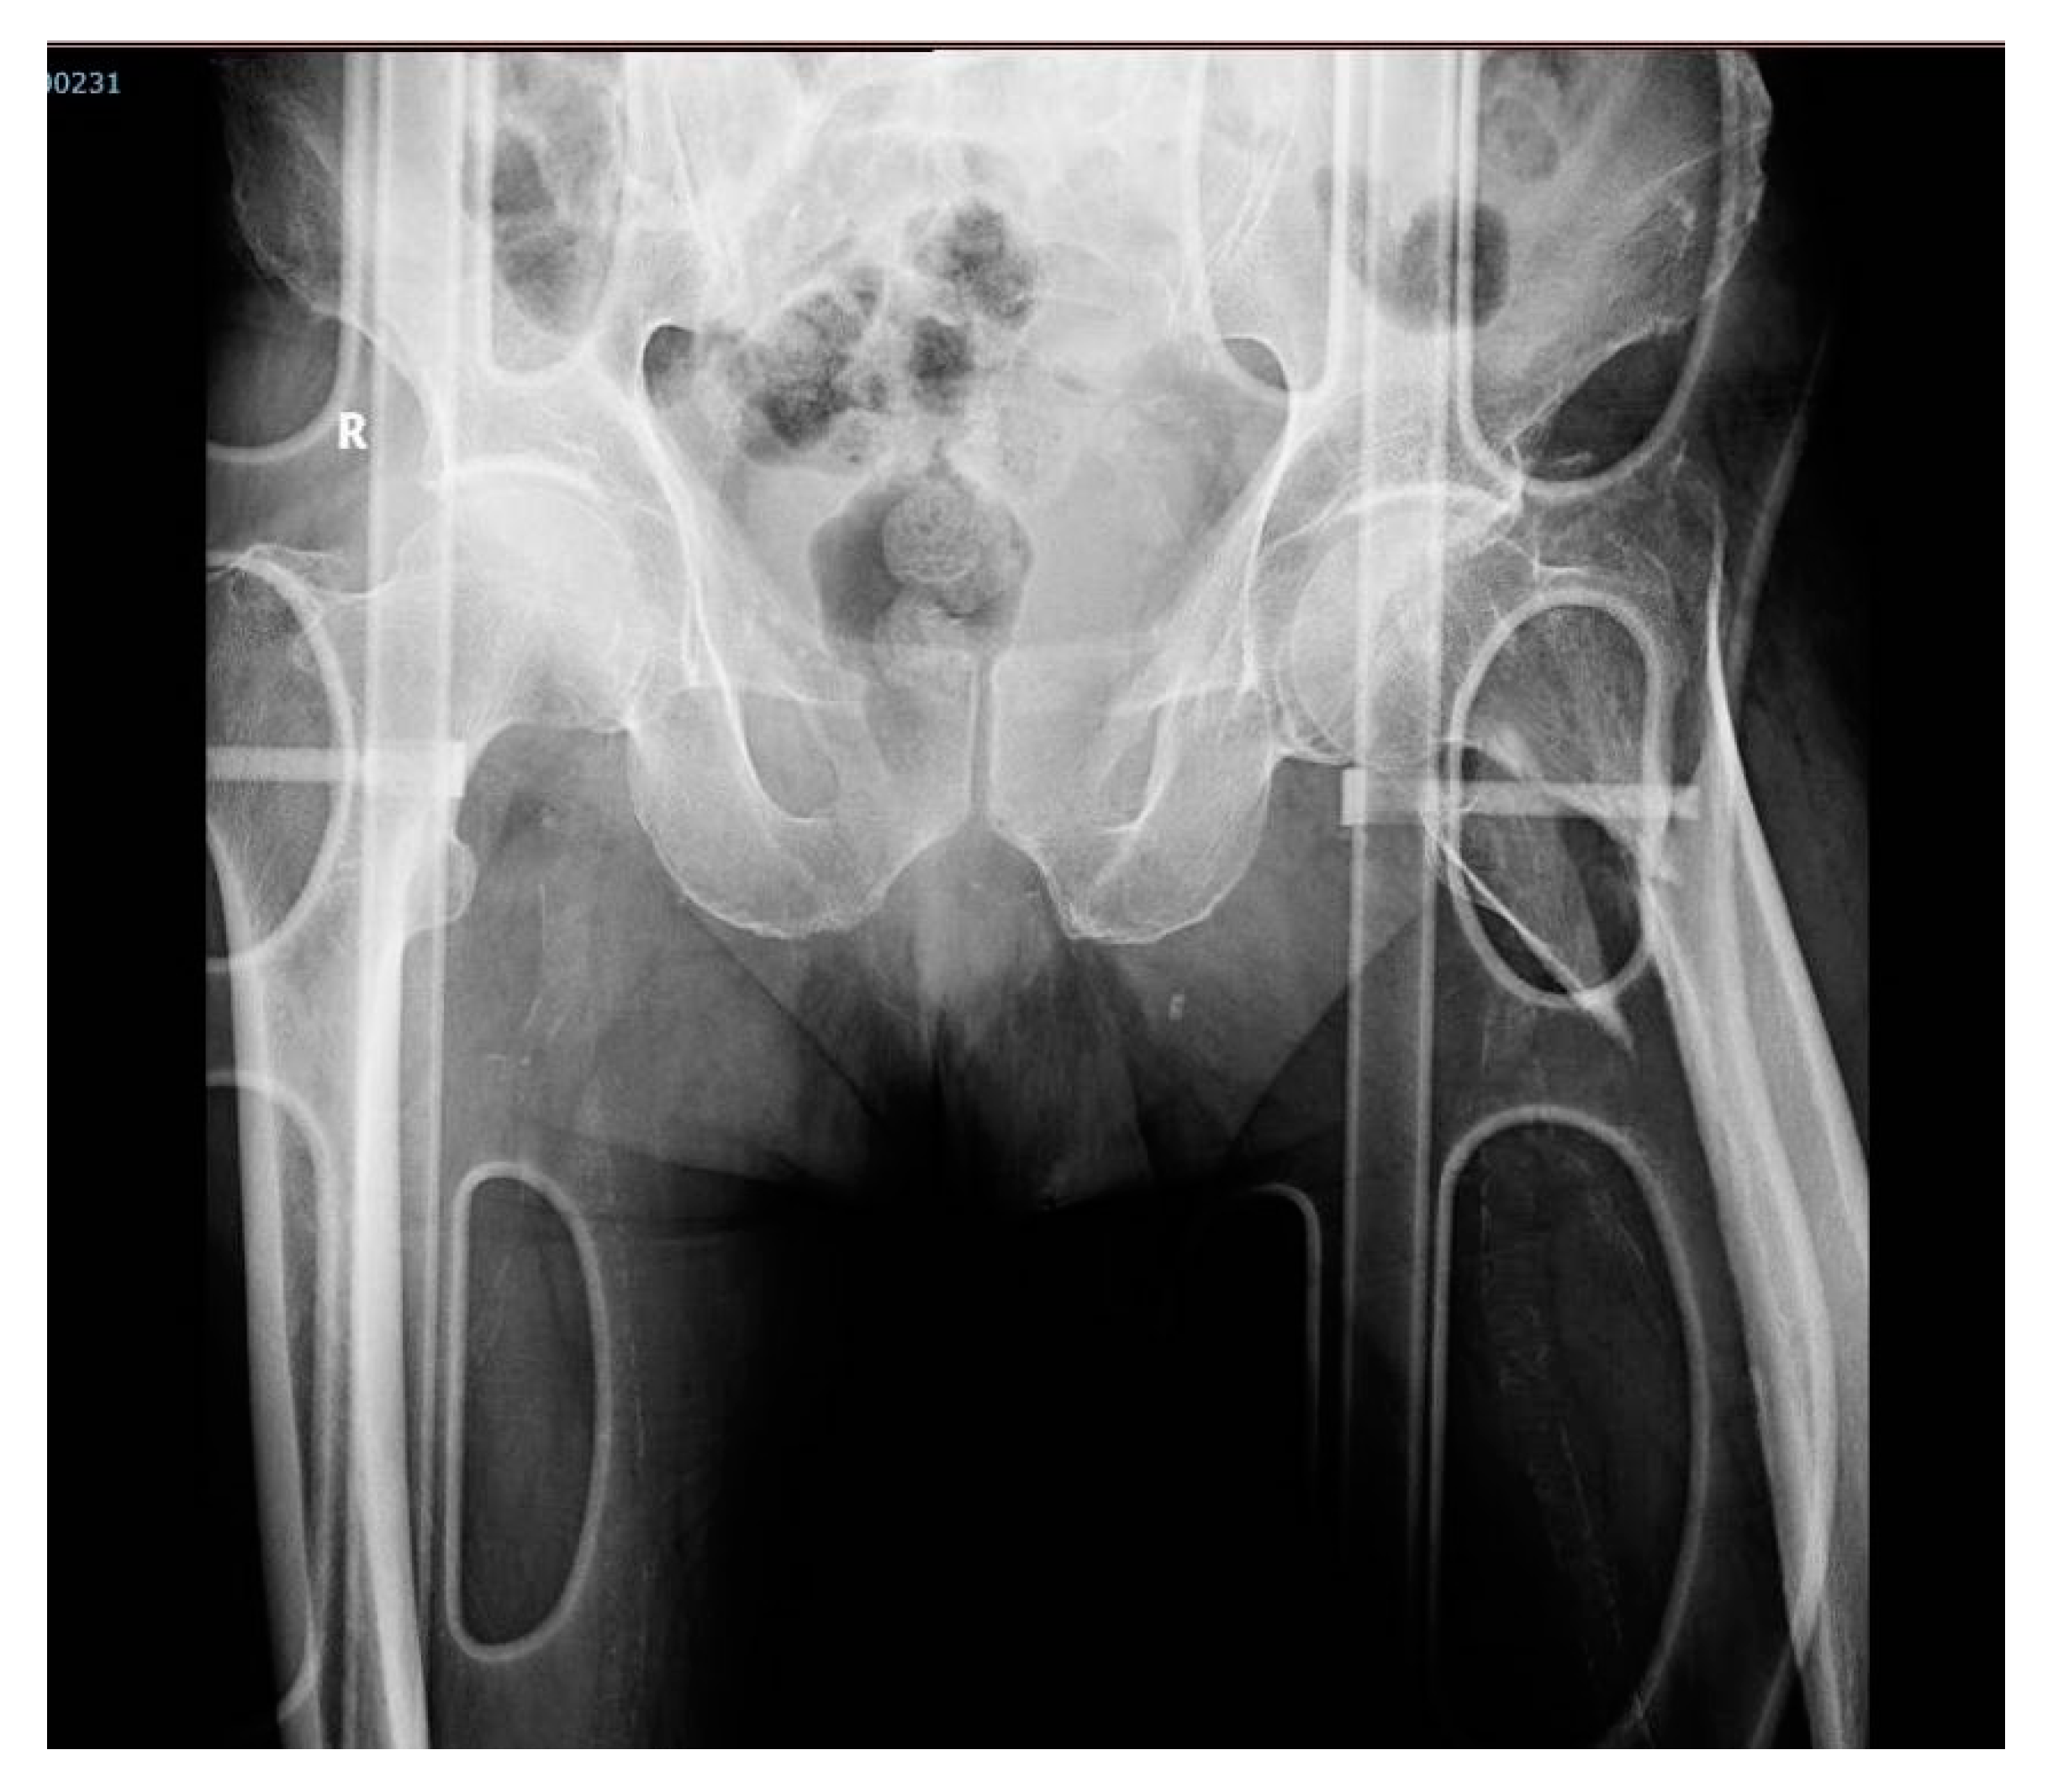

An underweight 87-year-old male subject with a history of hypertension and dementia, presented an accidental fall at home and was rushed to the local emergency county hospital on the same day. Upon admission, he presented 147/75 mmHg blood pressure, 60 bpm heart rate, SpO2 98%, and a temperature of 36.9 °C. A hip X-ray was performed, revealing a left pertrochanteric femur fracture (Figure 4). In addition, a nasopharyngeal swab specimen for SARS-CoV-2 was collected.

Figure 4. Pelvic X-ray upon arrival, in anteroposterior incidence. Description: Male subject on gurney. Right hip with minimal narrowing of the joint space. Left hip showing a left comminuted femur fracture in the upper ⅓ segment, with displaced bone fragments and minimum angulation.